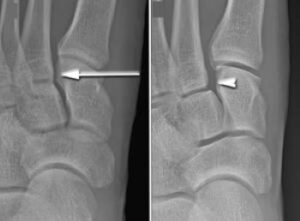

(Left) In this non-weightbearing X-ray, the Lisfranc injury does not show any abnormal widening (arrow). (Right) The tear of the Lisfranc ligament is more evident in this weightbearing stress X-ray, showing a widening of the joint.